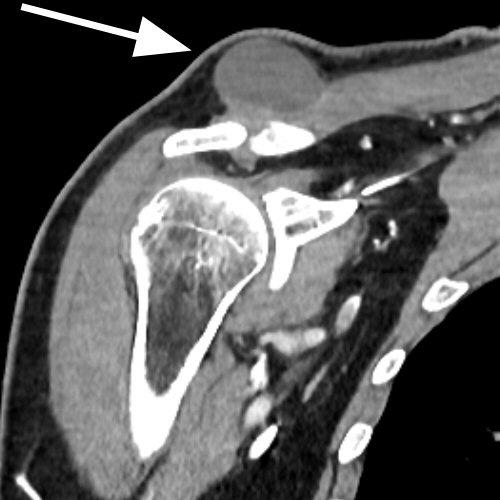

Vid kronisk rotatorkuffskada kan det utvecklas en flera cm stor, eftergivlig s.k. geysercysta i anslutning till AC-leden. Det beror på att ledvätska från axelleden läckt ut subkutant.

Geysercysta vid höger AC-led